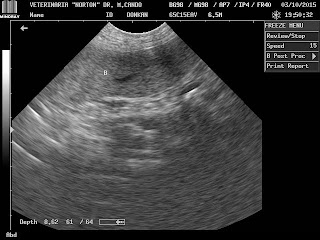

CIRUGÍA GENERAL Y DE TEJIDOS BLANDOS, TRAUMATOLOGÍA Y ORTOPEDIA, CARDIOLOGÍA, RAYOS X, ECOGRAFÍAS, LABORATORIO CLÍNICO....DR. MARCELO E. CANDO L. M.V.Z. -ESTAMOS UBICADOS AL SUR DE QUITO EN LAS CALLES HOPPE NORTON S-928 Y ADRIÀN NAVARRO, A UNA CUADRA DEL PATRONATO MUNICIPAL SAN JOSÈ. INFORMES AL 02-2648 115 -0984992384